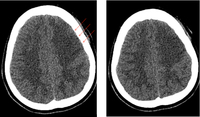

CT brain showing subarachnoid hemorrhage from a ruptured posterior cerebral artery aneurysm (2 of 2)

Courtesy of Dr Salah Keyrouz; used with permission

CT brain showing subarachnoid hemorrhage from a ruptured posterior cerebral artery aneurysm (1 of 2)